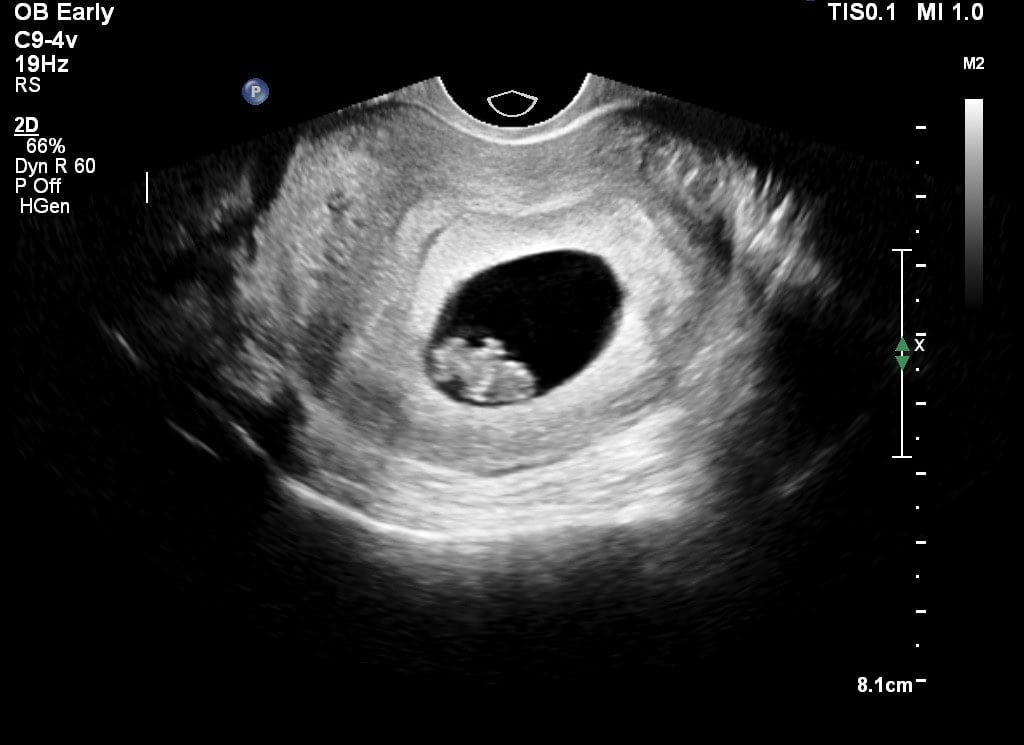

During a blood loss ultrasound, we examine the cause of the blood loss and look for peculiarities and whether the baby’s heart is beating. Usually the blood loss is harmless and nothing is wrong. Sometimes, unfortunately, the midwife determines that there is no heart beating or that the embryo is not developing properly. This is called a miscarriage.